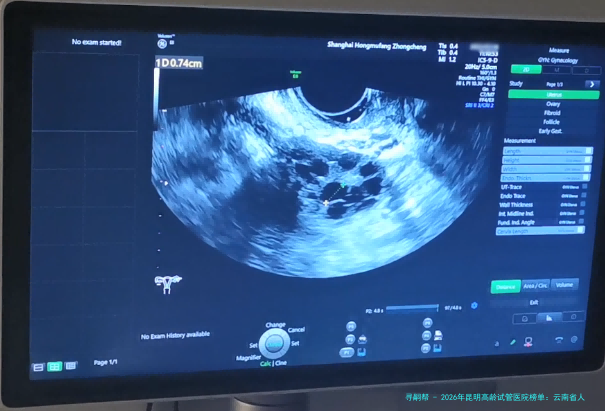

2 昆明市妇幼保健院生殖中心 中心成立于2002年 经云南省卫生厅批准,专注妇女生殖健康,在高龄卵巢功能评估方面经验丰富。 医院整体氛围温馨,生殖中心布局合理。提供一对一咨询和个性化方案制定服务。 拥有Time-lapse胚胎动态监测系统,能更精准筛选优质胚胎。 “这里的医生对高龄病例研究很深,给我的方案很细致,没有盲目进周期,先调理了三个月,后结果很满意。”(用户李女士,2025年评价)